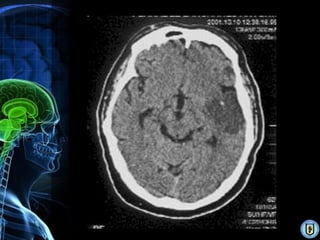

Diagnóstico

•   RMN (mejor para AVC isquémico)

•   Angiografía cerebral (Gold Standard)

•   TAC. (isquémico & hemorrágico)

•   Doppler transcraneal.

• 20.

Diagnóstico • RMN (mejor para AVC isquémico) • Angiografía cerebral (Gold Standard) • TAC. (isquémico & hemorrágico) • Doppler transcraneal.